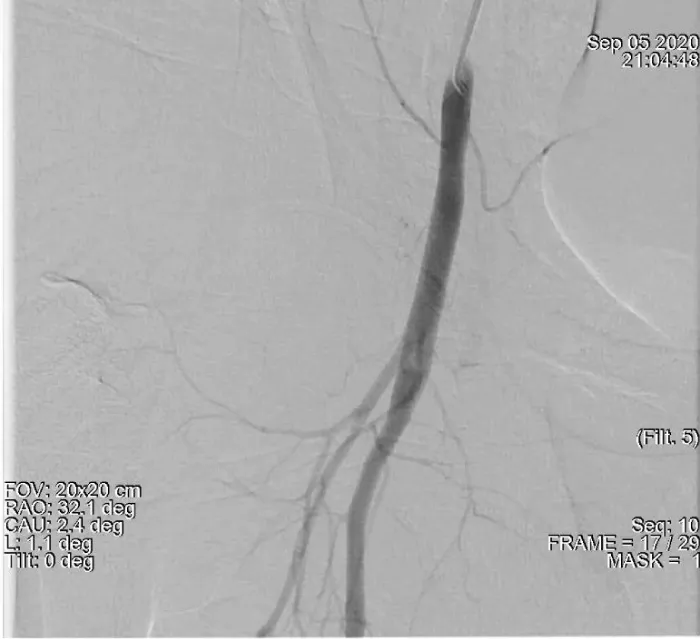

Post balloon tamponade angiogram revealed a complete sealing of the leakage with no further extravasation of contrast (Figure 4).

Download Image

Figure 4: Post balloon tamponade angiogram indicating complete sealing of the leakage.